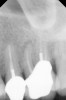

Clinical procedure: If apical bone loss is present (Figure 1) a collagen/gelatin sponge (eg, Gelfoam®, Pfizer Inc., www.pfizer.com) can be placed apically so that the MTA can be delivered to the desired working length. (Any other surgical resorbable sponge would also work, such as OraPlug® [Salvin Dental Specialties, www.salvin.com], Surgifoam® [Midwest Dental, www.mwdental.com], or Surgispon® [Aegis Lifesciences, www.surgispon.com]). This is done by taking a small piece (2 mm x 2 mm) of the resorbable sponge and pushing it down to and through the root apex with an endodontic file. Once this is done, MTA is packed down the canal with a custom-fitted cone. The clinician can use a rubber stopper on the gutta-percha cone to know the exact length of MTA placed in the apical third (Figure 2). Once the apical third is sealed with 3 mm to 5 mm of MTA, the remaining coronal canal space can be back-filled using a warm gutta-percha technique (Figure 3).

Fig 2. MTA placed in the apical third.

Figure 2

Fig 3. Postoperative radiograph.

Figure 3